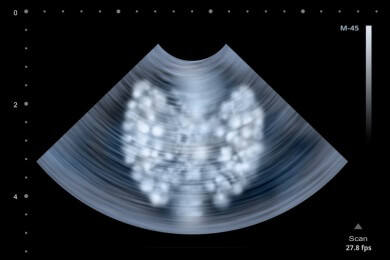

Viele Menschen haben kleine Knötchen in der Schilddrüse. Der Arzt spricht in diesem Zusammenhang von "Struma" und kann durch eine genau ...